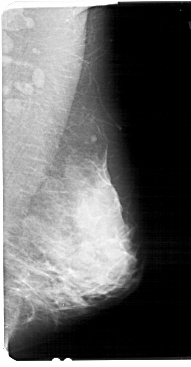

A_1449_1.LEFT_CC

LEFT_CC LINES 5356 PIXELS_PER_LINE 2626 BITS_PER_PIXEL 12 RESOLUTION 43.5 OVERLAY